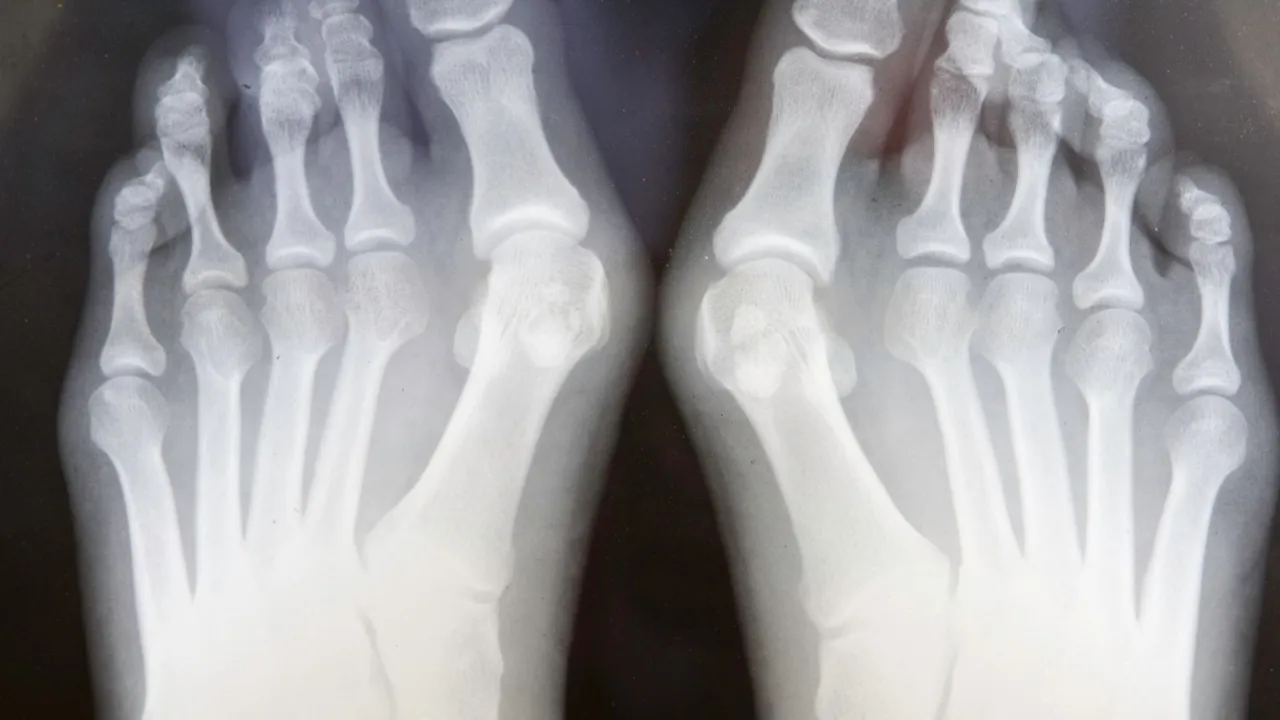

To bardzo ważne, abyśmy mieli jasność: moczenie stóp, choć niezwykle pomocne, jest metodą wspomagającą i łagodzącą objawy, ale nie leczy samej deformacji kostnej haluksa. Haluks to strukturalna zmiana w stopie, która wymaga często bardziej zaawansowanych interwencji, jeśli chcemy ją całkowicie skorygować.

Celem tych zabiegów jest przede wszystkim przyniesienie ulgi w bólu, zmniejszenie obrzęku i poprawa komfortu życia. Nie możemy oczekiwać, że regularne kąpiele sprawią, że haluks zniknie. Moim zdaniem, kluczowe jest realistyczne podejście. Traktujmy moczenie stóp jako cenną część codziennej rutyny dbania o zdrowie stóp, która pozwala nam funkcjonować z mniejszym dyskomfortem, a nie jako cudowne lekarstwo na przyczynę problemu. To uzupełnienie, a nie zastępstwo dla ewentualnej konsultacji z ortopedą.